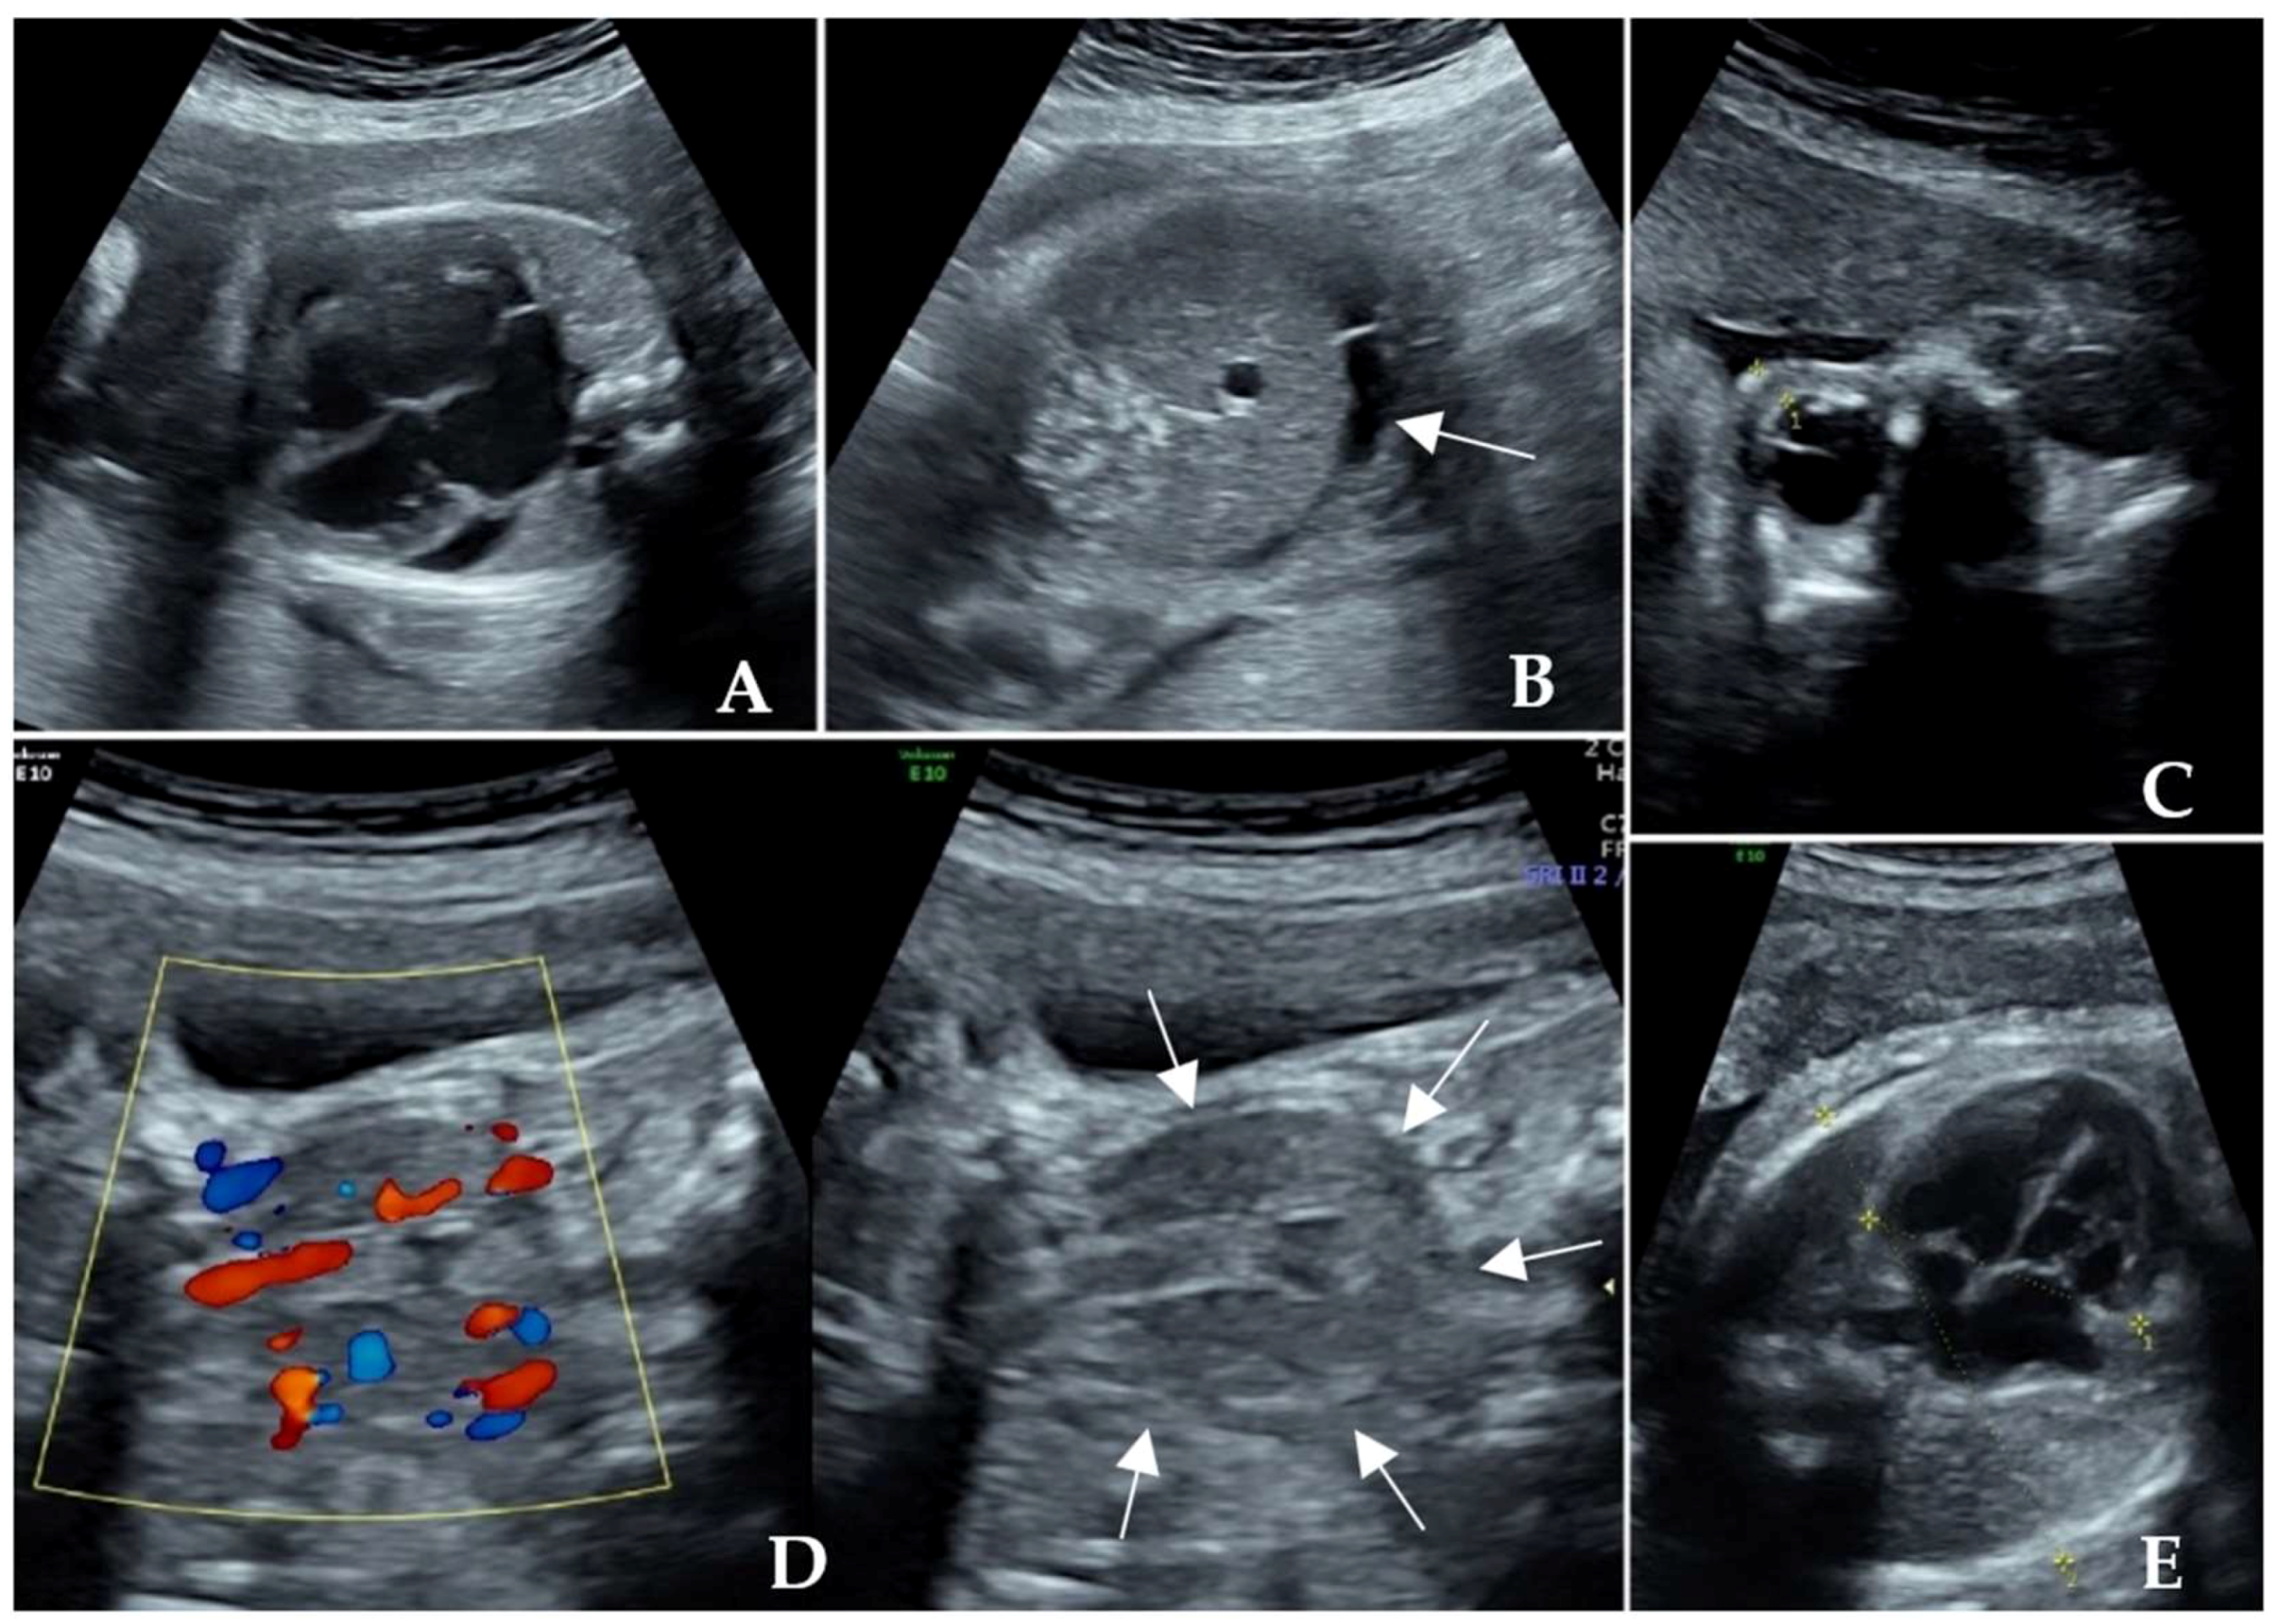

| Fetal manifestations | Fetal cardiac enlargement, pericardial effusion and cardiac hypertrophy, FGR, tachycardia, proptosis, and ventriculomegaly | Fetal tachycardia, enlarged heart and pericardial effusion, tricuspid regurgitation, oligohydramnios, and minor renal dysplasia |

| Weeks of gestation at presentation | 22+ weeks | 23+ weeks |

| Fetal thyroid status | Thyroid diffusely enlarged with abundant blood flow, hyperthyroidism (TSH 0.018 μIU/mL and TRAb 32.74 IU/L) | Fetal thyroid gland congested, hyperthyroidism (TSH 0.09 μIU/mL and TRAb 31.9 IU/L) |

| Significant signs of response | The fetal heart rate returned to the normal range 10 days later. The pericardial effusion and cardiothoracic ratio were relieved. | The fetal heart rate returned to normal at the 26th gestational week. Oligohydramnios, cardiac enlargement, pericardial effusion, and thyroid hyperemia were resolved. |

| Conditions of delivery | Spontaneous delivery at 36+6 weeks of gestation, 1900 g | Spontaneous delivery at 36 weeks of gestation, 3000 g |

| Outcome of the newborn | Neonatal hyperthyroidism, alive and healthy | Neonatal hyperthyroidism, alive and healthy |